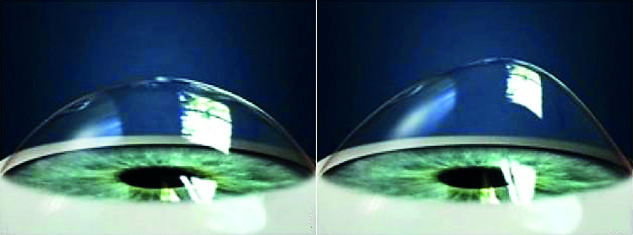

Svolta innovativa nel campo dell’oftalmologia grazie a un nuovo strumento tecnologico: con la Teranostica (nuovo paradigma di terapia guidata dalla diagnostica) arriva la certezza di arrestare la progressione del cheratocono, una patologia oculare che colpisce i giovani e che rappresenta a livello mondiale la prima causa di trapianto di cornea negli under 40 nel mondo (ne soffre tra l’1% e il 2% della popolazione mondiale, circa 100 milioni di persone). L’importante innovazione arriva da Regensight, startup innovativa che ha inventato e sviluppato la cura definitiva di questa patologia, grazie appunto alla tecnologia teranostica. Il progetto è stato presentato all’interno dello Spazio Attivo della Regione Lazio “Roma Tecnopolo”, gestito da Lazio Innova.

Il progetto nasce dall’analisi dei fratelli Marco e Giuseppe Lombardo – co-fondatori della startup, rispettivamente medico oculista e ingegnere biomedico – partendo dai limiti dell’attuale procedura di cross-linking corneale per la cura del cheratocono, quali l’elevata variabilità di efficacia (tra il 10% e il 90%) e l’incapacità di comprenderne l’esito terapeutico se non dopo almeno un anno di controlli medici. Combinando ricerca medica e razionalità ingegneristica, i fratelli Lombardo hanno creato un sofisticato strumento di teranostica. Grazie all’implementazione di tecniche di diagnostica molecolare per immagini, la piattaforma di teranostica abilita l’operatore a raggiungere l’effetto terapeutico desiderato grazie all’applicazione della giusta dose della molecola terapeutica di riboflavina (vitamina B2) nella cornea (l’esatta dose terapeutica) e alla sua foto-attivazione precisa con la giusta dose di energia di luce UV-A nelle aree più deboli della cornea. In definitiva, la tecnologia trasformativa combina la terapia di precisione alla diagnostica avanzata per immagini in un unico strumento che assiste e guida il medico oculista ad eseguire un trattamento personalizzato per arrestare in modo definitivo la progressione della patologia in ogni paziente, superando i limiti delle terapie attuali per la cura del cheratocono. Al termine della sperimentazione clinica in corso, il nuovo dispositivo sarà ufficialmente operativo entro la prossima estate. Il progetto “Chromo4Vis” di Vision Engineering Italy, società madre di Regensight, ha ricevuto un finanziamento a valere sul bando della Regione Lazio “KETs Tecnologia Abilitanti”. Regensight ha in seguito ricevuto la concessione di un contributo per lo sviluppo del progetto “Kervis” a valere sull’avviso pubblico “Pre-Seed”. Grazie a Lazio Innova ed ai finanziamenti ricevuti, entrambi a valere sul Por Fesr 2014-2020, sono state completate le attività di ricerca & sviluppo pre-competitivo dell’azienda, ricevendo un supporto anche nel processo di certificazione CE dei dispositivi medici ed all’autorizzazione alla convalida clinica dei prodotti inventivi nel Trial Clinico.